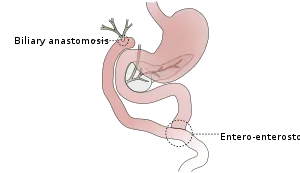

A surgically created passage between the common bile duct and the jejunum in a procedure called a choledochojejunostomy, can be carried out to relieve the symptoms of biliary obstruction as well as allows the bile duct to drain.[5]